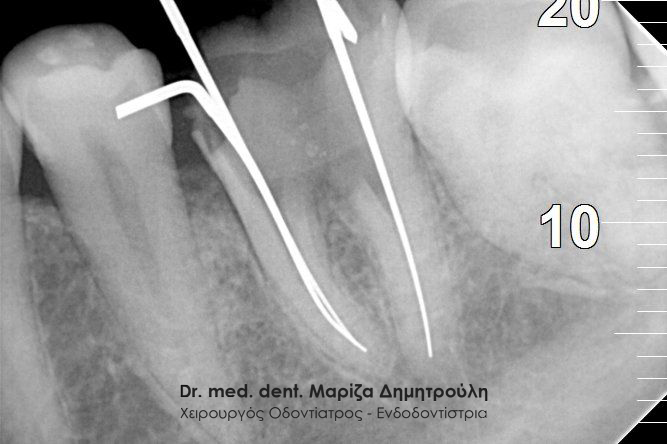

Έγινε η κλινική και ακτινογραφικά εξέταση του δοντιού. Στην αρχική ακτινογραφία που πραγματοποιήθηκε πριν τη διάνοιξη του δοντιού παρατηρήθηκε ο έντονος εκτροχισμός του δοντιού ανάμεσα στις ρίζες. Η ακτινογραφική αυτή εικόνα γεννά υποψίες για πιθανή διάτρηση του δοντιού στο συγκεκριμένο σημείο. Διάτρηση ενός δοντιού κατά τη διάρκεια της απονεύρωσης μπορεί να προκληθεί όταν ο οδοντίατρος “ανοίγει” (τροχίζει) το δόντι στην προσπάθεια του να εντοπίσει τις ρίζες του δοντιού (ριζικοί σωλήνες). Είναι δηλαδή πιθανόν το δόντι να τροχιστεί σε άλλο σημείο από αυτό που εντοπίζονται οι ρίζες του δοντιού, με αποτέλεσμα να δημιουργηθεί μία τρύπα στο δόντι. Η τρύπα αυτή ονομάζεται διάτρηση.

Μετά από τη χορήγηση τοπικής αναισθησίας και την τοποθέτηση ελαστικού απομονωτήρα ακολούθησε η διάνοιξη του δοντιού. Αμέσως μετά την αφαίρεση του προσωρινού σφραγίσματος παρατηρήθηκε έντονη και απότομη αιμορραγία του δοντιού, η οποία προερχόταν από ένα συγκεκριμένο σημείο. Η κλινική αυτή εικόνα επιβεβαίωσε τις υποψίες για διάτρηση του δοντιού. Εντοπίστηκε το σημείο της διάτρησης και έγινε έλεγχος με μία ακτινογραφία. Στη συνέχεια πραγματοποιήθηκε η αποκατάσταση της διάτρησης με ειδικό υλικό και εντοπίστηκε ο τρίτος σωλήνας του δοντιού. Η όλη διαδικασία επιβεβαιώθηκε με τη λήψη ακτινογραφίας.

Αξίζει να σημειωθεί ότι η ασθενής μετά το πρώτο ραντεβού στο ιατρείο (στο οποίο βρέθηκε ο τρίτος ριζικός σωλήνας και “έκλεισε” το σημείο της διάτρησης) δεν πονούσε πλέον και το δόντι ήταν ασυμπτωματικό. Στην επόμενη συνεδρία το δόντι παρασκευάστηκε με ειδικά μηχανοκίνητα εργαλεία ενδοδοντίας και απολυμάνθηκε με ειδικά υγρά διακλυσμών. Η διαδικασία ολοκληρώθηκε με την έμφραξη των ριζικών σωλήνων (ριζών του δοντιού) με γουταπέρκα. Σε επόμενη επίσκεψη έγινε η αποκατάσταση του δοντιού με έμφραξη ρητίνης.

Εντοπισμός του τρίτου ριζικού σωλήνα